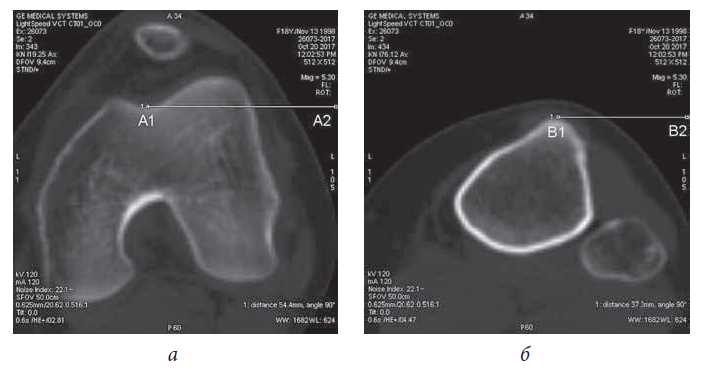

Slope of the patella

To measure the slope of the patella, a section was used through the femoral block (the same as in the TT–TG measurement) as well as a section through the patella in the projection of the maximum diameter. In some cases, these sections coincided (Fig. 2). Two lines were then drawn: one through the patella in the frontal plane (A1–A2), and another through the posterior margins of the femoral condyles (B1–B3). The angle between the two lines represents the slope angle of the patella. In 90% of patients with patellar instability, this angle is more than 20°. In this group of pediatric patients, arthroscopic stabilization of the patella was performed with a lateral release, and in 10% of patients with a normal slope angle of the patella (less than 20°) the arthroscopic stabilization without a lateral release was conducted. Patients with a large angle of patella slope had a more pronounced pain syndrome at rest and during dislocation. We believe this is due to the fact that a large slope angle of the patella (more than 25°) at the time of dislocation and subluxation is associated with greater damage to the cartilage of the patella and the lateral condyle of the femur.

Fig. 2. Measurement of patella tilt